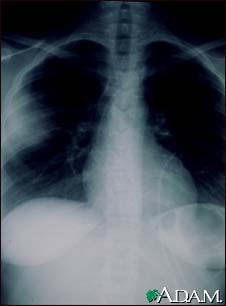

Aspergillosis - chest X-ray

Aspergillosis is a fungal infection. The fungus invades and destroys tissue. This type of infection usually occurs in immunocompromised individuals. Here, a chest x-ray shows that the fungus has invaded the lung tissue. The lungs are usually seen as black areas on an x-ray. The cloudiness on the left side of this x-ray is caused by the fungus.